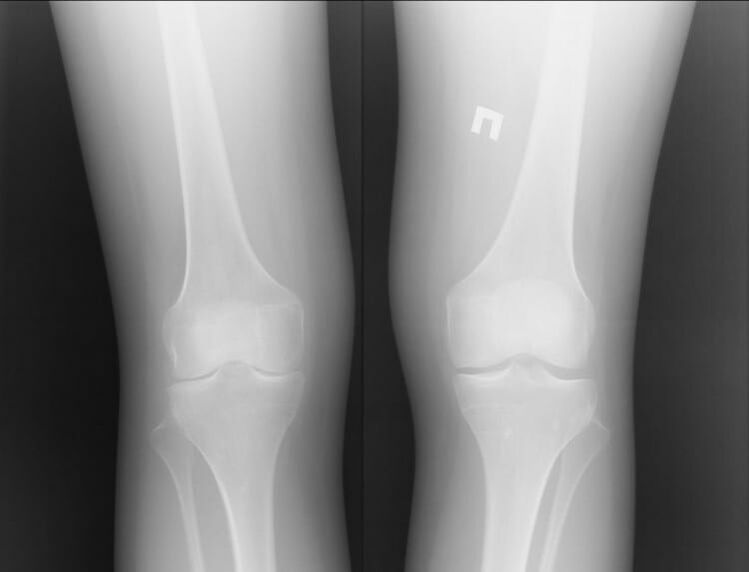

Of course, both of these diseases are quite serious and it is difficult to say which one is worse.However, we can consider the example of a problem in the knee joint.With arthritis, that is, with inflammatory processes, the patient can be assisted.

Most often this is due to other infections that occur in the human body.If they heal and the inflammation of the joint is removed, then the knee arthritis will no longer bother you.

Arthrosis is a completely different story.It is an independent disease caused by problems in cartilage tissue.Often this cannot be done without surgical intervention.This is followed by another long recovery process.

Therefore, we can say that arthritis is a more serious disease.However, arthritis can cause the first disease.Both diseases should not neglect.It is better to contact a specialist immediately.